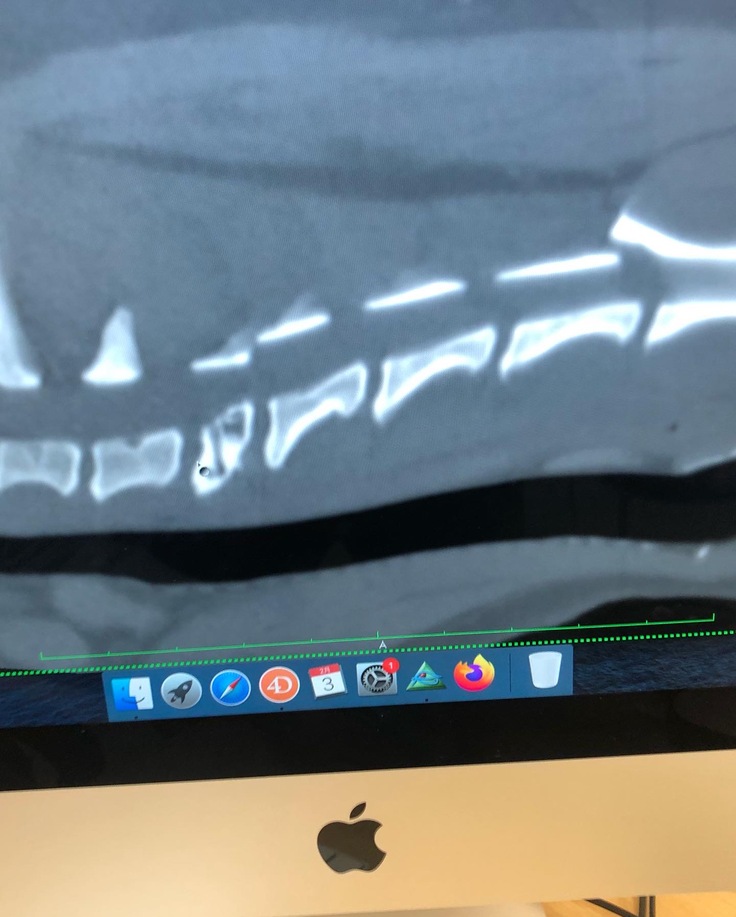

※検査画像 下段の真ん中付近 穴の開いた骨が確認できます。

頚椎6番になります。この骨の8/2日 現在の状態です、

奇跡的に温存出来ています。